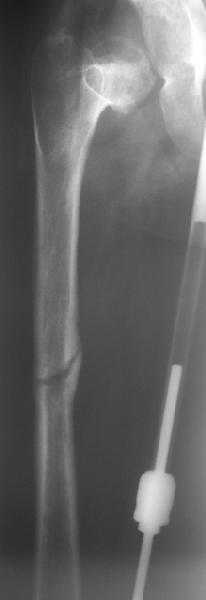

Поступила к нам в отделение. В отделении первым этапом был наложен аппарат внешней фиксации для низведения  бедра. 30.09.08 интрамедуллярный стержень удален. Вторым этапом планируется эндопротезирование. В настоящее время у больной имеется контрактура коленного сустава, с амплитудой движений в пределах 30 градусов., и выраженный остеопороз вертлужной впадины и проксимального отдела бедра. Больныя пердвигается самостоятельно с опорой на здоровую ногу и костыли. <br><br>

Какие проблемы при эндопротезиовании в этих условиях ожидать, и как с ними бороться? Еще и диафиз сросся не очень крепко, опасаемся, как бы не сломать. Очень выражен местный остеопороз, может быть, сделать все-таки цементный протез? Хотя 18 лет всего. Спасибо.